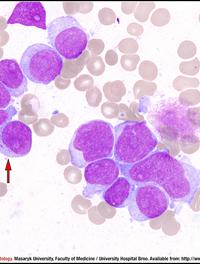

Les syndromes myélodysplasiques (SMD) constituent un groupe hétérogène d’hémopathies caractérisées par une dysplasie de la moelle osseuse [...]

Les syndromes myélodysplasiques (SMD) de faible risque correspondent aux catégories risque faible et risque intermédiaire 1 de l’IPSS [...]